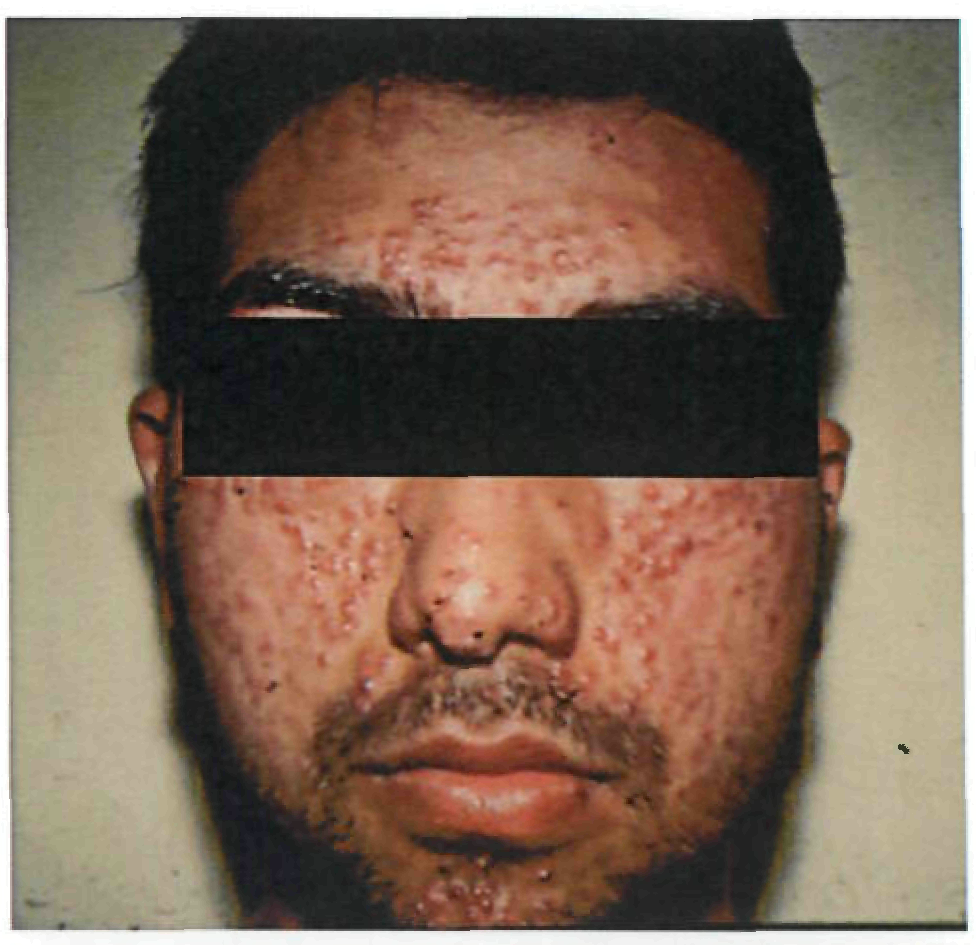

Период высыпаний

На 3-4-й день болезни температура тела снижается до субфебрильной, одновременно на коже головы (прежде всего на лице) и на слизистых оболочках полости рта, гениталий, конъюнктивы, роговицы глаз появляются необильные элементы сыпи. Энантема на слизистых оболочках полости рта обычно предшествует появлению экзантемы. Первые элементы сыпи обычно появляются на лице, быстро распространяясь на верхние конечности, а затем - на туловище и нижние конечности, поражая ладони и подошвы. Распространение экзантемы имеет центробежный характер - на туловище элементов меньше, чем на лице и конечностях.

Высыпания эволюционируют через стадии:

- макула (пятно) (1-2 дня);

- папула (узелок) (1-2 дня);

- везикула (пузырек, заполненный прозрачной жидкостью) (1-2 дня);

- пустула (гнойничок) с пупковидным вдавлением в центре (5-7 дней);

- корочка (7-14 дней).

В 70-80% случаев сыпь характеризуется мономорфностью, в остальных случаях может отмечаться полиморфизм [38]. На одном участке кожи сыпь всегда мономорфна.

В 95% случаев сыпь поражает лицо, в 75% - ладони и подошвы, что является отличительным признаком заболевания. Также поражаются слизистые оболочки полости рта (в 70% случаев), половые органы (30%), конъюнктива и/или роговица (20%). У части пациентов имеет место проктит с поражениями перианальной области изолированно или в сочетании с высыпаниями в области гениталий [39]. Количество элементов сыпи варьирует от единичных до нескольких тысяч [13].

При формировании пустул вновь повышается температура тела, нередко до 39-40°С, состояние больных значительно ухудшается, развиваются тахикардия, артериальная гипотензия, одышка, сильный зуд кожи. Возможны диарея, лимфаденит (чаще шейный и паховый).